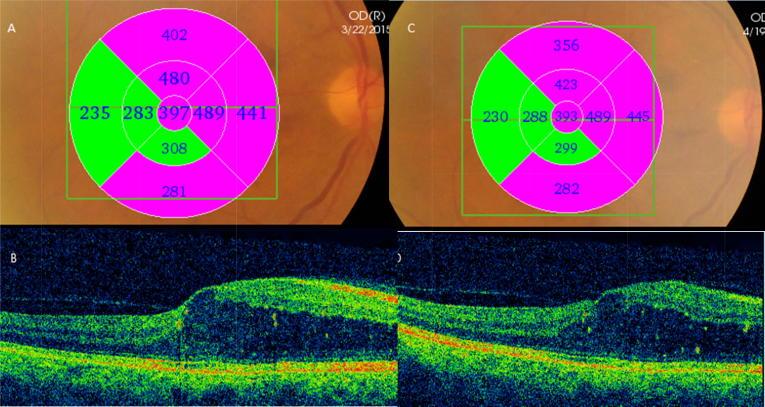

Fifty eyes with persistent DME were randomly allocated to intravitreal injection of 500 µg/0.1 ml of diclofenac ( = 20) or 1.25 mg/0.05 mL of bevacizumab ( = 20) or to non-treatment (10 eyes). Preoperative and postoperative visual acuity, central, paracentral macular thickness and intraocular pressure (IOP) were recorded and compared between the three groups up to 4 weeks.

Diclofenac and bevacizumab groups showed statistically significant reduction in central and paracentral macular thickness (diclofenac:  = 0.006, 0.02 and bevacizumab:  = 0.02, 0.01), without statistically significant difference between the two groups. The two groups showed no statistically significant difference in mean visual acuity or mean line improvement. Mean visual acuity improvement didn't reach statistical significance in either group. Diclofenac group showed statistically significant reduced IOP ( = 0.02). Control eyes did not show any change in mean visual acuity, macular thickness or IOP.

将50只患有持续性糖尿病黄斑水肿的眼睛随机分为三组,分别接受玻璃体内注射500μg/0.1ml双氯芬酸(n = 20)、1.25mg/0.05ml贝伐单抗(n = 20)或不进行治疗(10只眼)。记录术前和术后的视力、黄斑中心和旁中心厚度以及眼压(IOP),并在三组之间比较长达4周的数据。

双氯芬酸组和贝伐单抗组的黄斑中心和旁中心厚度均有统计学意义的降低(双氯芬酸组:P = 0.006,0.02;贝伐单抗组:P = 0.02,0.01),两组之间无统计学意义的差异。两组在平均视力或平均视力改善行数方面无统计学意义的差异。两组的平均视力改善均未达到统计学意义。双氯芬酸组的眼压有统计学意义的降低(P = 0.02)。对照组的平均视力、黄斑厚度或眼压均无变化。